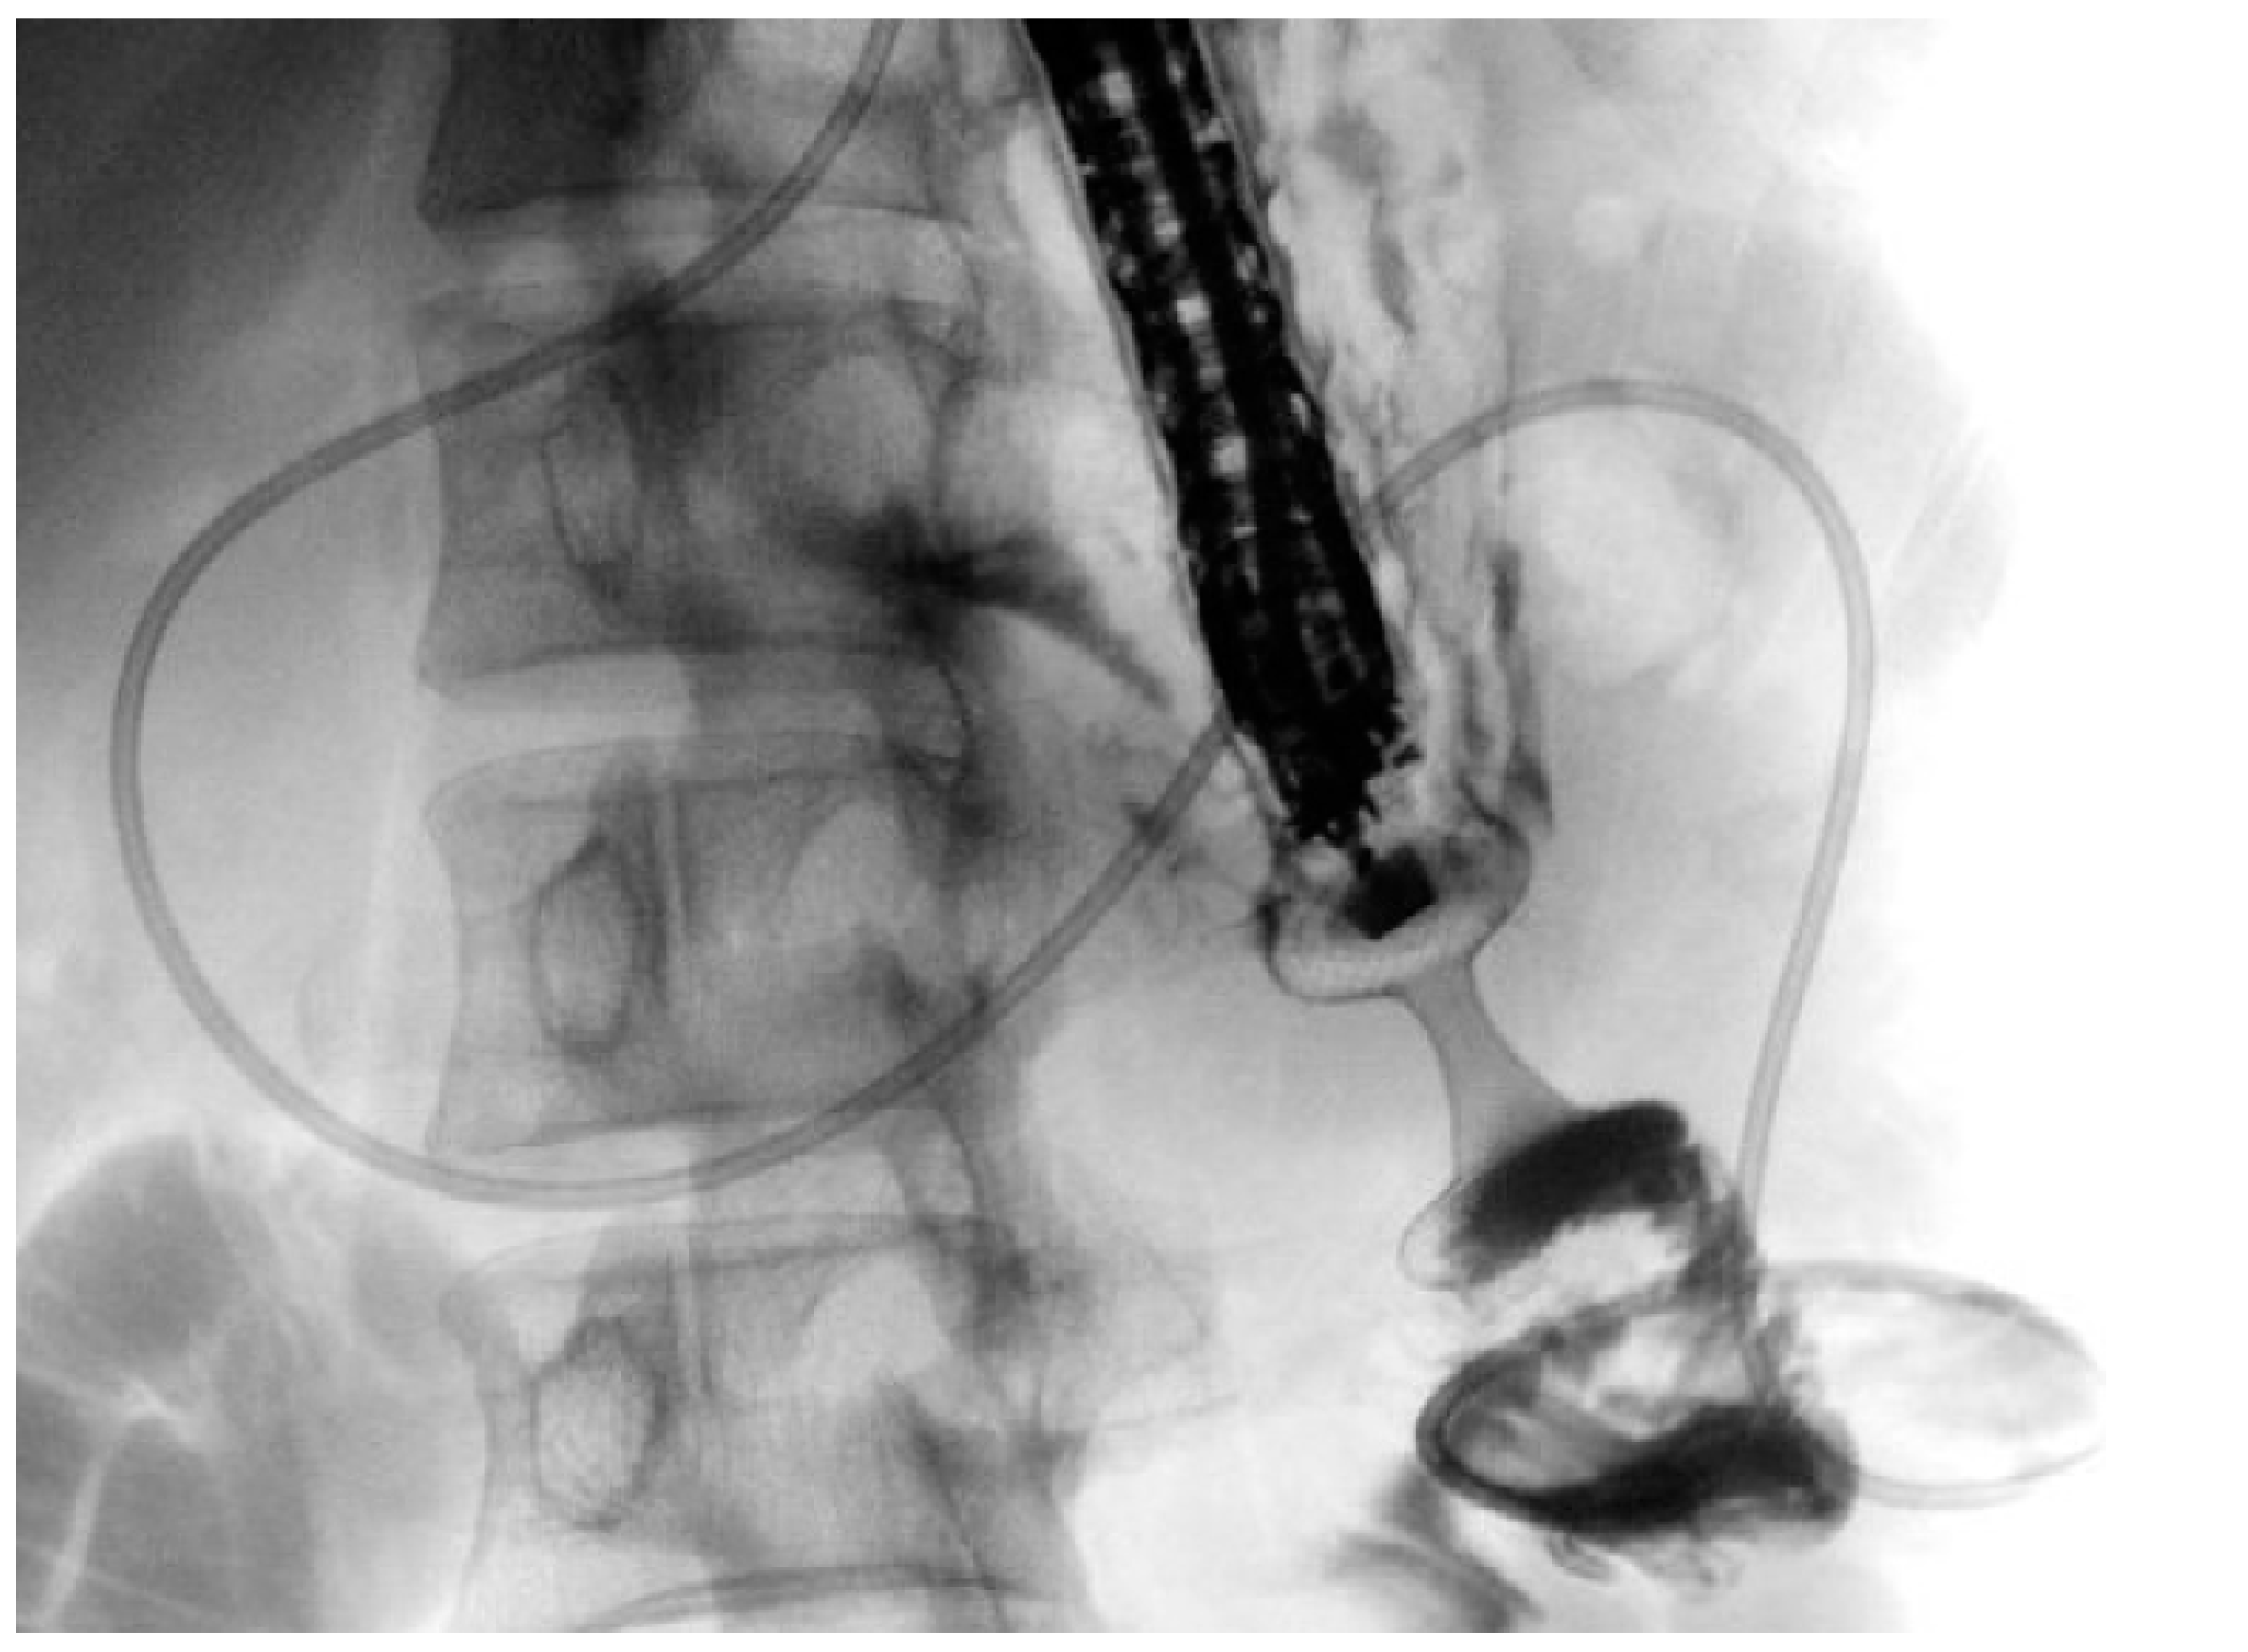

EUS-HGS is likely the most technically demanding EUS-BD procedure, primarily due to the required familiarity with multiple devices and the need for frequent device exchanges, as well as the limited operative space within the intrahepatic bile ducts [33]. During the last years, there has been a growing interest in technical standardization and in developing new devices, particularly dedicated SEMS (dedicated ec-PC-SEMS), to improve the safety profile of EUS-HGS (Figure 2) [33,34].

The first technical step in EUS-HGS is selecting the puncture site, typically performed under EUS guidance in segment 2 (B2) or segment 3 (B3) of the left hepatic lobe [33]. The bile duct should have a minimum diameter of >2 mm for expert operators or >5 mm for non-experts. Puncture is usually performed using a 19-gauge FNB needle. Following puncture, contrast injection through the needle is essential to perform a cholangiogram to confirm proper positioning and proceed. Some operators also aspirate bile to prevent pneumobilia and ensure entry into the bile duct. Next, a guidewire is advanced into the bile duct and directed distally, ideally through the papilla. The hepatic–gastric tract is then created by advancing an electrocautery-enhanced cystotome (typically 6Fr in caliber) from the stomach into the bile duct. Alternatively, pneumatic dilation of the tract can be performed. Finally, a dedicated PC-SEMS (variable length from 80 to 100 mm) is advanced over the guidewire, with the uncovered distal portion (approximately 30% of the entire length) deployed in the bile duct and the proximal fully covered portion (approximately 70% of the entire length) in the gastric lumen [33].